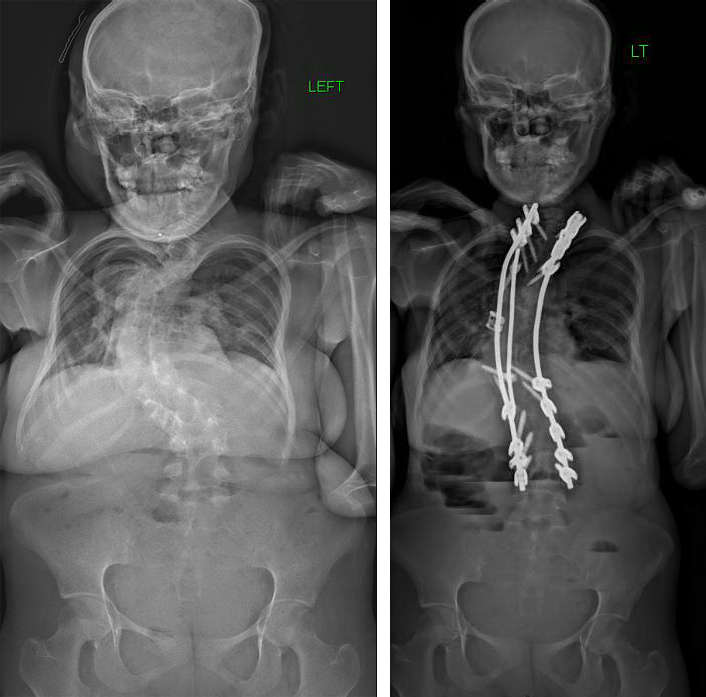

After meeting eight surgeons who could not treat her severe scoliosis, Patricia almost gave up hope of living without pain. But, the team at NewYork-Presbyterian didn’t hesitate—they performed reconstruction and fusion to straighten her spine and heal her nerves, giving her the hope that nobody else could.